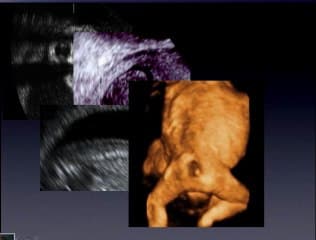

Après avoir rappelé les recommandations du CTE, Jean Philippe Bault considère que la meilleure étude du membre inférieur se fera au premier trimestre par le mode conventionnel, volumique ou omniview. Il cite ensuite de nombreuses pathologies, ostéochondrodysplasie, ostéogénèse imparfaite, sirénomélie, ectrodactylie....

Après un rappel anatomique sur l’aspect échographique du diaphragme l’auteur insiste sur l’intérêt des coupes frontales 3D ,du doppler couleur (ductus venosus) et décrit les signes indirects permettant le dépistage des hernies diaphragmatiques gauche et droite.